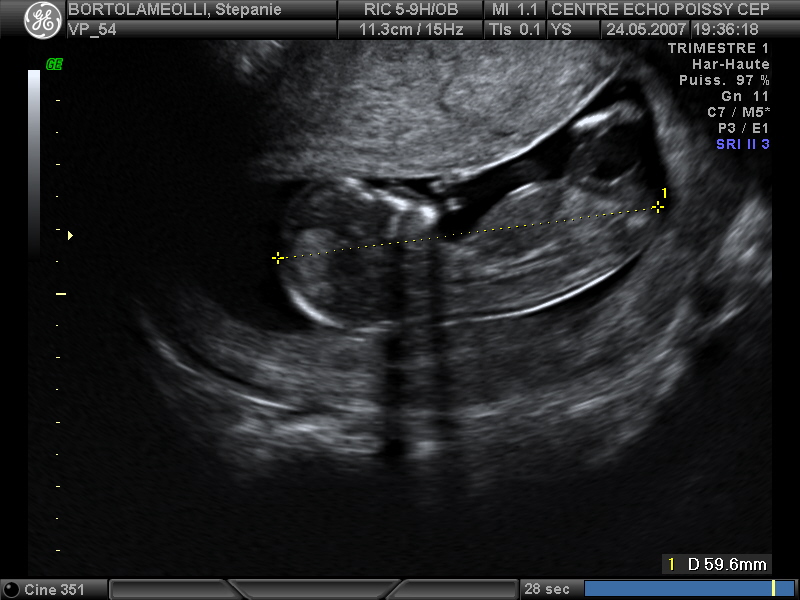

Echographies

Mai 2007